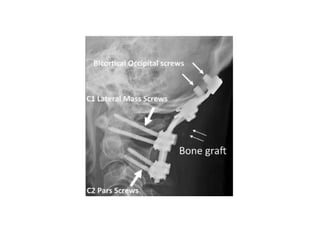

Surgical stabilization

• C1 – type II odontoid combination # with d >

5mm.

• C1 – hangman combination # C2-3 angulation

> 11 degree

• 66.

Surgical stabilization • C1– type II odontoid combination # with d > 5mm. • C1 – hangman combination # C2-3 angulation > 11 degree